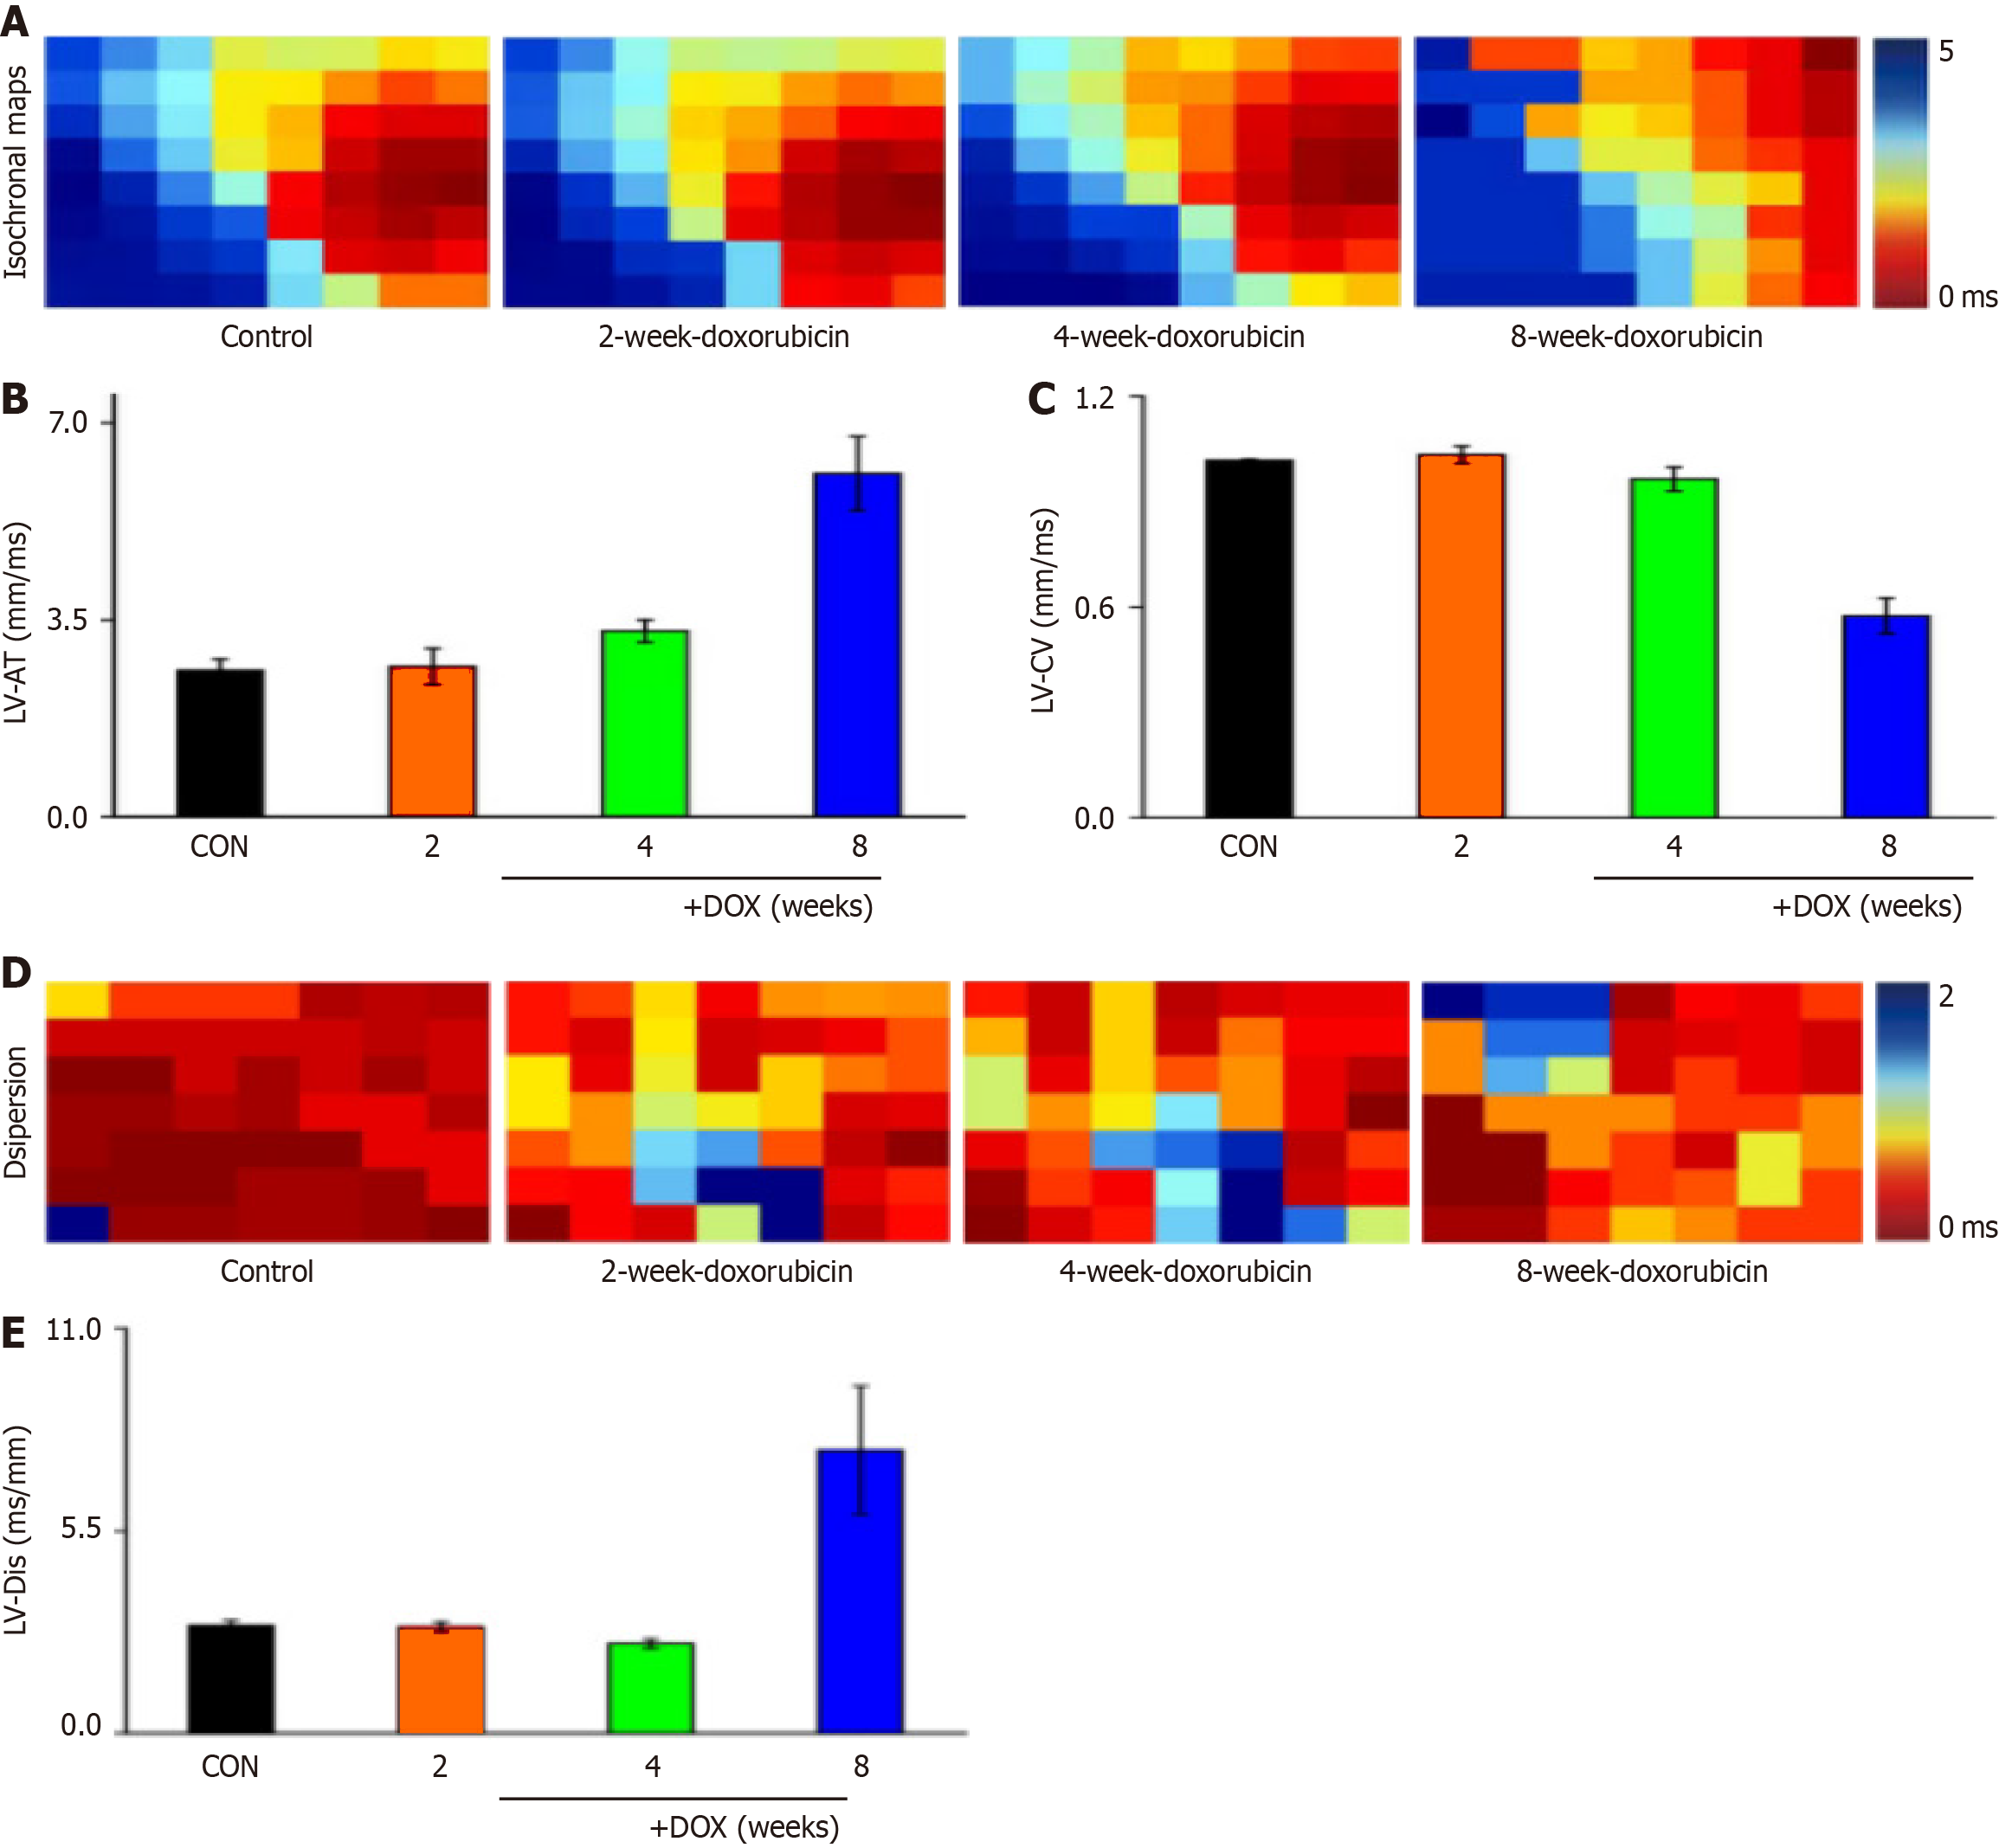

The left ventricular signals of rat hearts were recorded with 64-channel pen electrodes. Under sinus rhythm, the effect of ventricular conduction time was obvious in the model group (Figure 2A), and the conduction changes were significantly different. Analysis of the left ventricular conduction time revealed that there was a tendency to prolong the conduction time after drug administration (Figure 2B), and there was no significant change in conduction velocity (Figure 2C).

Conduction dispersion was a concern in the study of arrhythmic disease mechanisms, and examination of cardiac conduction dispersion in DOX model rats in sinus rhythm revealed a significant effect on cardiac conduction dispersion in the model group (Figure 2D), with a tendency for prolongation of ventricular conduction dispersion in sinus rhythm (Figure 2E).